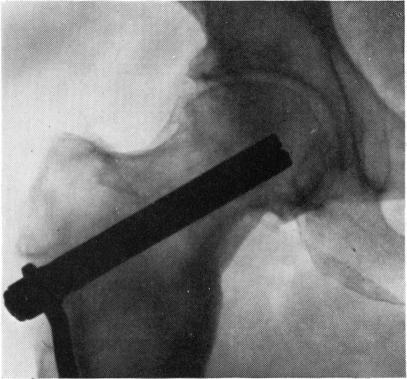

THE ARREST OF EARLY PRIMARY OSTEOARTHRITIS OF THE HIP BY OSTEOTOMY.

Proc R Soc Med. 1963 Dec;56(12):1051-60. doi: 10.1177/003591576305601204.